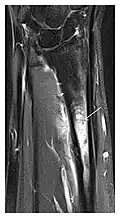

Figure 8: Proximal diaphyseal fatigue fracture of the tibia in a 20-year-old man with a history of regular jogging. (a) Lateral radiograph shows no obvious fracture lines but a subtle localized medial tibial cortex periosteal reaction (arrows). (b) Sagittal reformatted CT image acquired 1-month after the radiograph shows a linear hypoattenuation in the tibial cortex (arrowhead), as well as obvious periosteal thickening (arrows). (c) Sagittal T2-weighted fat-saturated image acquired the same day shows an area of hyperintensity spreading over the proximal tibia (arrows), which is consistent with the presence of proximal tibial fracture.[1]